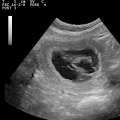

Trächtigkeits- / Welpentagebuch